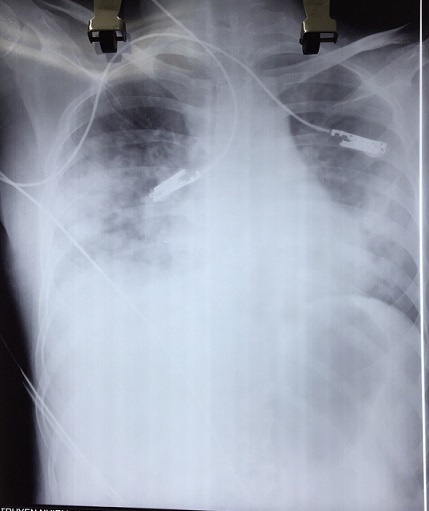

| Hình ảnh chụp X-quang viêm phổi của bệnh nhân . Ảnh: MT. |

Phim chụp X-quang và các xét nghiệm cho thấy bệnh nhân bị biến chứng viêm phổi nặng sau thủy đậu, trên nền lupus ban đỏ hệ thống/hoại tử đầu chi. Bệnh nhân đang được điều trị tích cực, phải thở oxy song tiên lượng rất dè dặt.